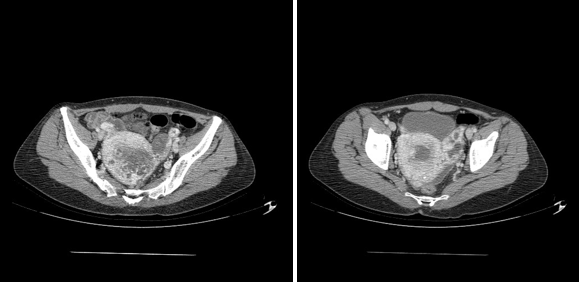

Figure 4 MRI image showing on the right a uterus increasing in size site of a heterogeneous intracavitary image extended to the left ovary.

And so, the pelvic MRI was in favor of a gestational trophoblastic tumor invading the serosa coming into contact with the ovary and the rectum posteriorly measuring 65*45mm associated with thrombosis of the left internal iliac vein and the homolate ovarian vein, just as a Hemoperitoneum of low abundance (Figure 4).

On a biological level, an HCG level of 124,856, then, the pelvic ultrasound showed an enlarged uterus with a hyper echogenic heterogeneous honeycomb image of 43x31mm, non-vascularized on Doppler, in favor of a Hydatidiform mole. With the presence at the fundal level of 2 heterogeneous images measuring 55x32mm and 20x16mm at the peripheral level, raising doubts about myometrial invasion, hence the realization of cross-sectional imaging to assess loco-regional extension (Figures 1–4).